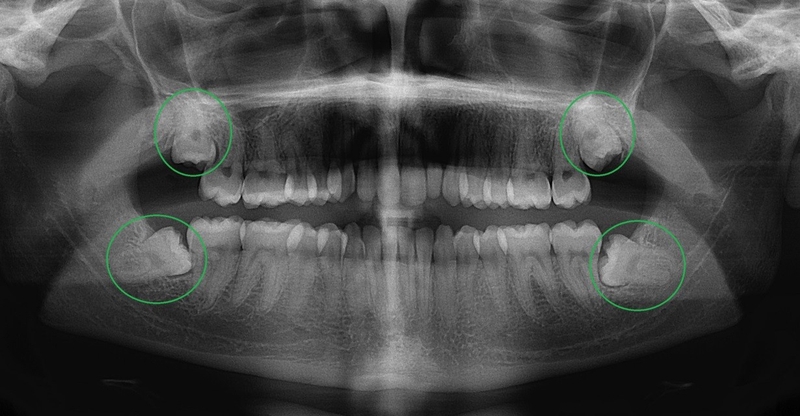

Mặt khác, việc nhổ 2 răng khôn cùng lúc được hay không còn tùy thuộc vào tình trạng sức khỏe của từng người. Trước khi tiến hành nhổ răng khôn, bác sĩ sẽ tiến hành thăm khám và chụp phim X - quang, phân tích tình trạng răng của bệnh nhân và đưa ra tư vấn cụ thể.

Nếu sức khỏe của bạn tốt thì có thể tiến hành nhổ 2 răng khôn cùng lúc thậm chí là 4 răng. Ngược lại, nếu sức khỏe của bạn không tốt khi đó, nhổ 2 răng khôn cùng lúc sẽ không được thực hiện. Thông thường bác sĩ sẽ chỉ định nhổ 2 răng khôn ở cùng một bên hàm trái hoặc phải để hạn chế việc tổn thương toàn hàm, không ảnh hưởng đến quá trình ăn nhai.

Trường hợp bác sĩ chỉ định nhổ 2 răng khôn nằm khác vị trí (ví dụ như một chiếc nằm bên trái, một chiếc nằm bên phải) dù nằm cùng một hàm hay không vẫn được bác sĩ đề xuất nhổ thành 2 lần.